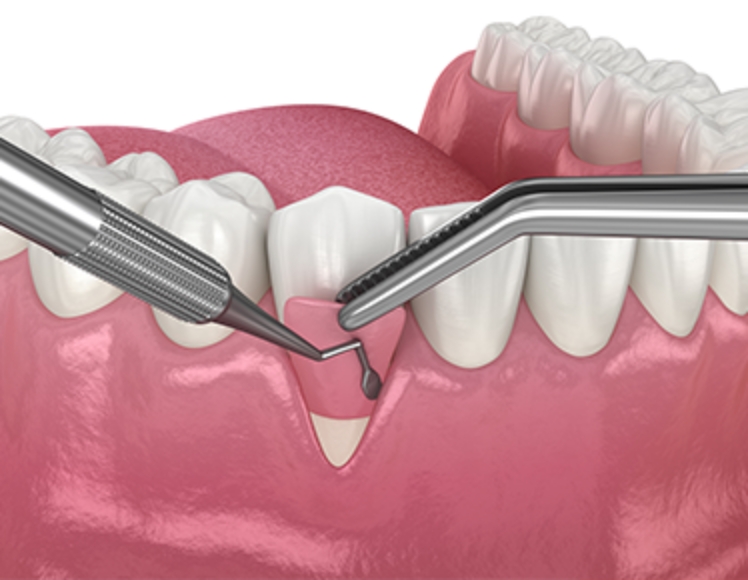

• Periodontal Disease専門医による 重度歯周病治療、 歯周組織再生療法で 歯を残します